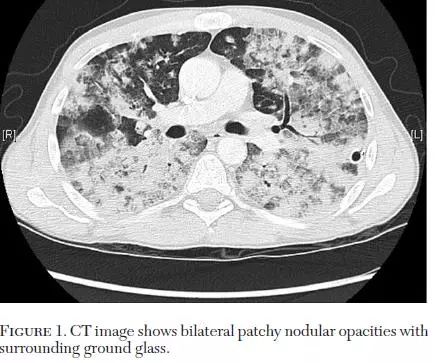

■ 加拿大,安大略省,优美的旅游城市汉密尔顿,麦克马斯特大学(McMaster University),报道一例,每天咳痰多达2000ml。

英文如下:A 46-year-old man presented with BAC with 2,000 mL of sputum production on a daily basis。

CT,双肺弥漫性病变(多发斑片、结节影、磨玻璃影),如下: